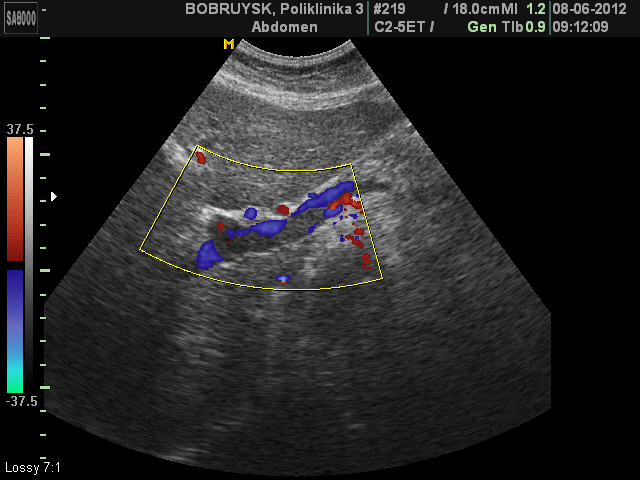

ЦДК, промб в левой ветви ВВ.